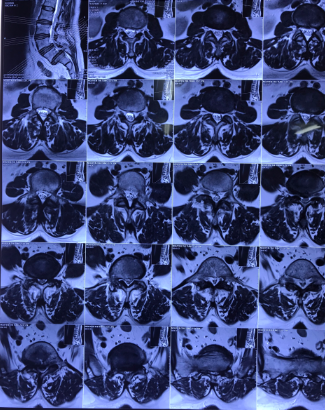

Bệnh nhân Nguyễn Thị T. (53 tuổi) tại Nghi Thuỷ - TX Cửa Lò xuất hiện tình trạng đau cột sống thắt lưng đã lâu, được điều trị bằng Y học cổ truyền và Phục hồi chức năng nhiều năm nay. Hiện tại, tình trạng đau tăng lên, đau tê dọc 2 chân, đi lại khó khăn, cơ lực 2 chân giảm. Sau khi tìm hiểu tham khảo nhiều đơn vị khác, chị T. được giới thiệu tới bệnh viện CTCHNA thăm khám và được chẩn đoán trượt đốt sống thắt lưng L5 độ III, thoát vị đĩa đệm L5S1 gây hẹp ống sống nặng, chèn ép rễ thần kinh L5 hai bên.

Hình ảnh: Cộng hưởng từ và X Quang bệnh nhân trước phẫu thuật